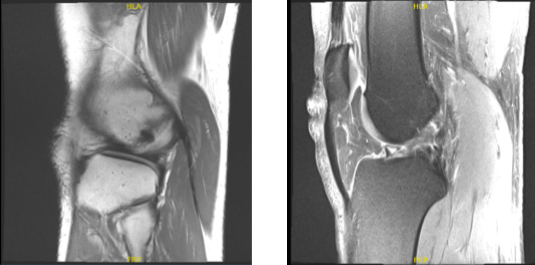

The patient is a 38-year-old guy who came into the office complaining of discomfort and instability in his right knee. He added that he had previously seen a doctor who diagnosed him with an ACL tear. A knee MRI was done which confirmed the absence of ACL. Physical examination was positive for ACL deficiency.

MRI right knee non-contrast